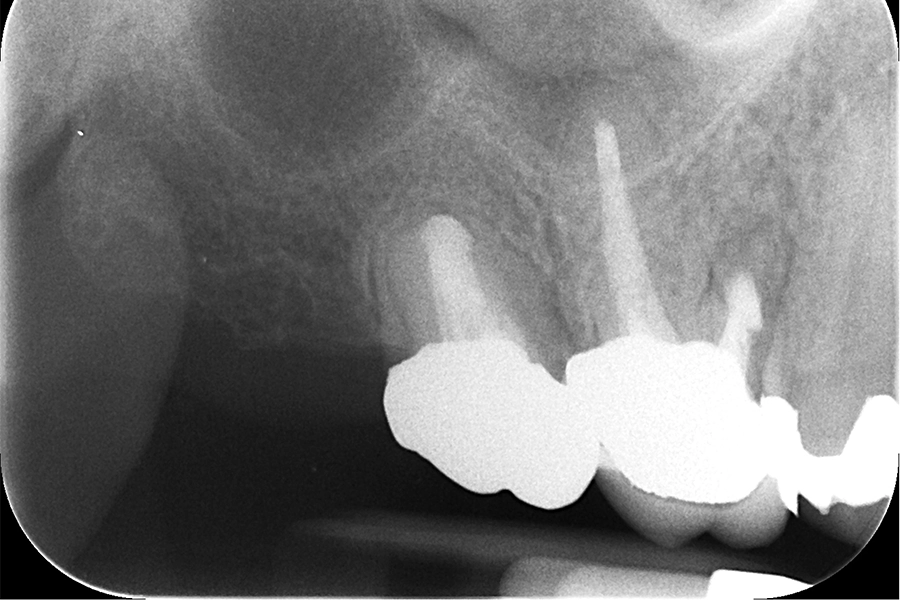

治療後